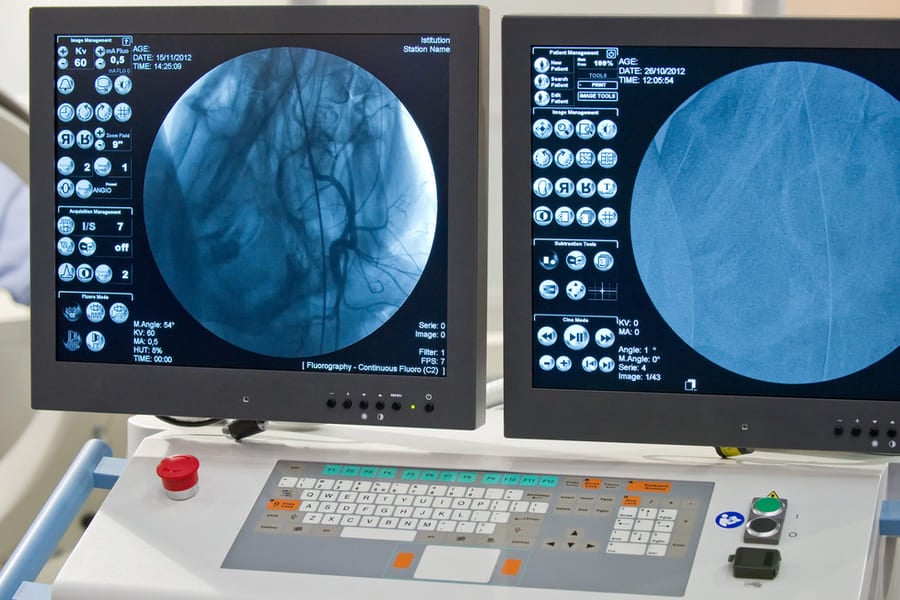

- Дигитална субтракционна ангиография (DSA) – техника, при която фоновите тъкани се премахват от изображението, за да останат видими само кръвоносните съдове. Това дава изключителна яснота и детайлност.

При класическата ангиография в артерия (най-често бедрената) се въвежда катетър. Чрез него се впръсква контрастно вещество, а рентгеновата апаратура записва изображения на кръвния поток. Процедурата е минимално инвазивна и обикновено пациентът се възстановява бързо.

В модерните болници съвременната ангиография често се комбинира с компютърна обработка на данните и създаване на 3D модели. Това дава възможност за изключително точна оценка и планиране на лечението.